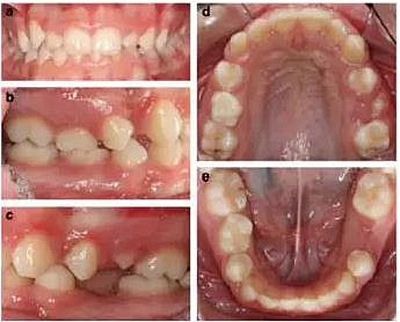

患者面型對稱,面上下比例對稱,輕度凸面型,鼻唇角正常;

輕度牙齦炎,口腔衛(wèi)生一般,無齲??;

右側(cè)II類磨牙關(guān)系和尖牙關(guān)系,左側(cè)I類磨牙關(guān)系和尖牙關(guān)系;

深覆合,前牙輕度不齊,下中線右偏2mm;

上下頜右側(cè)第二乳磨牙存,其余乳磨牙已脫落;